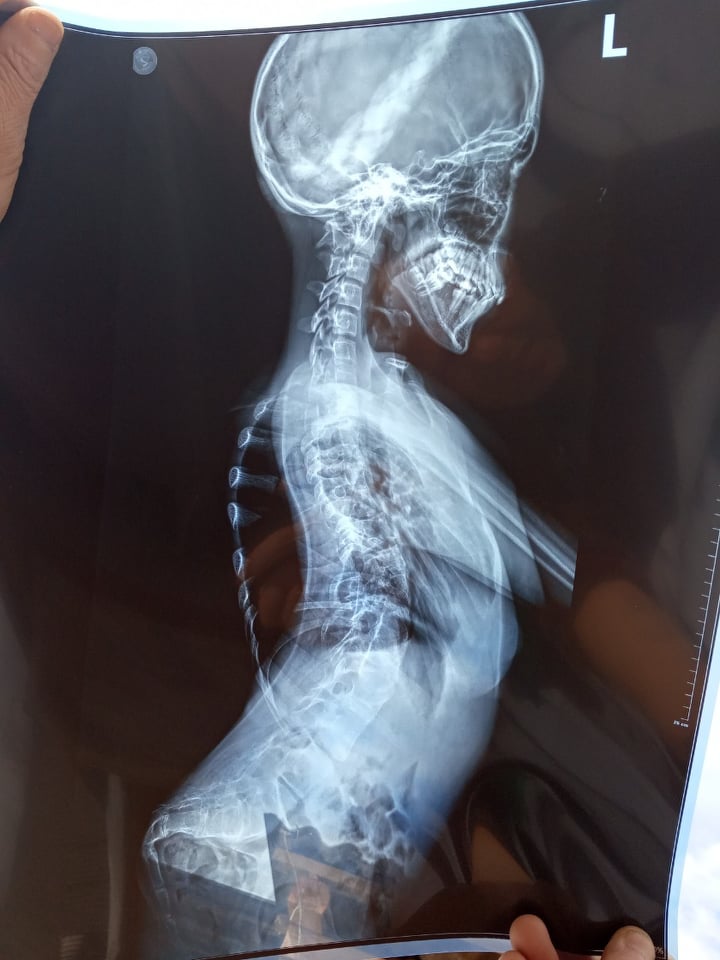

14-річна Тетяна Бабич із села Смеречка, що у Самбірському районі, потребує негайної дорогавартісної операції. У дівчинки вроджена вада хребта, зрослися хребці грудного та поперекового відділів. Від такого викривлення, Тетянці стискає легені, вона терпить невимовний біль. Допомогти може лише оперативне втручання, на яку дуже потрібні гроші.

Як пояснюють лікарі матері дівчинки – у неї вроджена аномалія хребта – зрощення хребців у грудному та поперековому відділах, простіше кажучи хребет поступово викривляє буквою «s». Крім того  у Тетянки у двох місцях зрощені по два ребра. Вся ця проблема не дає дитині дихати, тисне на легені. Дівчинка відвідує звичайну школу, але з кожним днем її дається це важче.

«Вона може просто пересуватися коридором в школі і раптом її щось сильно здавлює в грудях, сковує рухи. Іноді просто задихається. Вночі спить лише на одному боці. Якщо у нормальної людини легені розвинені до позначки 8, то у моєї дочки до 4. Ми придбали для неї бігову доріжку, працювали багато, займалися, але розтягнути їх змогли лише до 6. Лікарі застерігають – йде до гіршого. Якщо цього процесу не зупинити, може бути непоправне», – додає мати дівчинки.